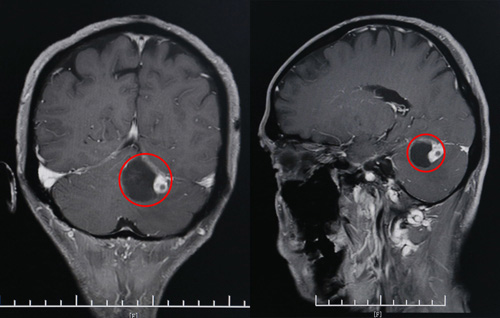

CT影像顯示,患者左側(cè)小腦囊實性占位(紅圈部分)

在家人的一再勸導下,黃先生還是決定去醫(yī)院走一趟。這不查不知道,一查嚇一跳——在當?shù)氐目h人民醫(yī)院,頭顱CT顯示,黃先生的左側(cè)小腦半球占位。

經(jīng)過進一步檢查后,黃先生左側(cè)小腦半球囊實性占位,考慮血管母細胞瘤可能大。院神經(jīng)外科專家團隊經(jīng)過討論后認為,患者有手術指征,考慮在全麻下行枕下入路小腦腫瘤切除術。但由于腫瘤位置較高,貼近小腦幕,手術風險較高。